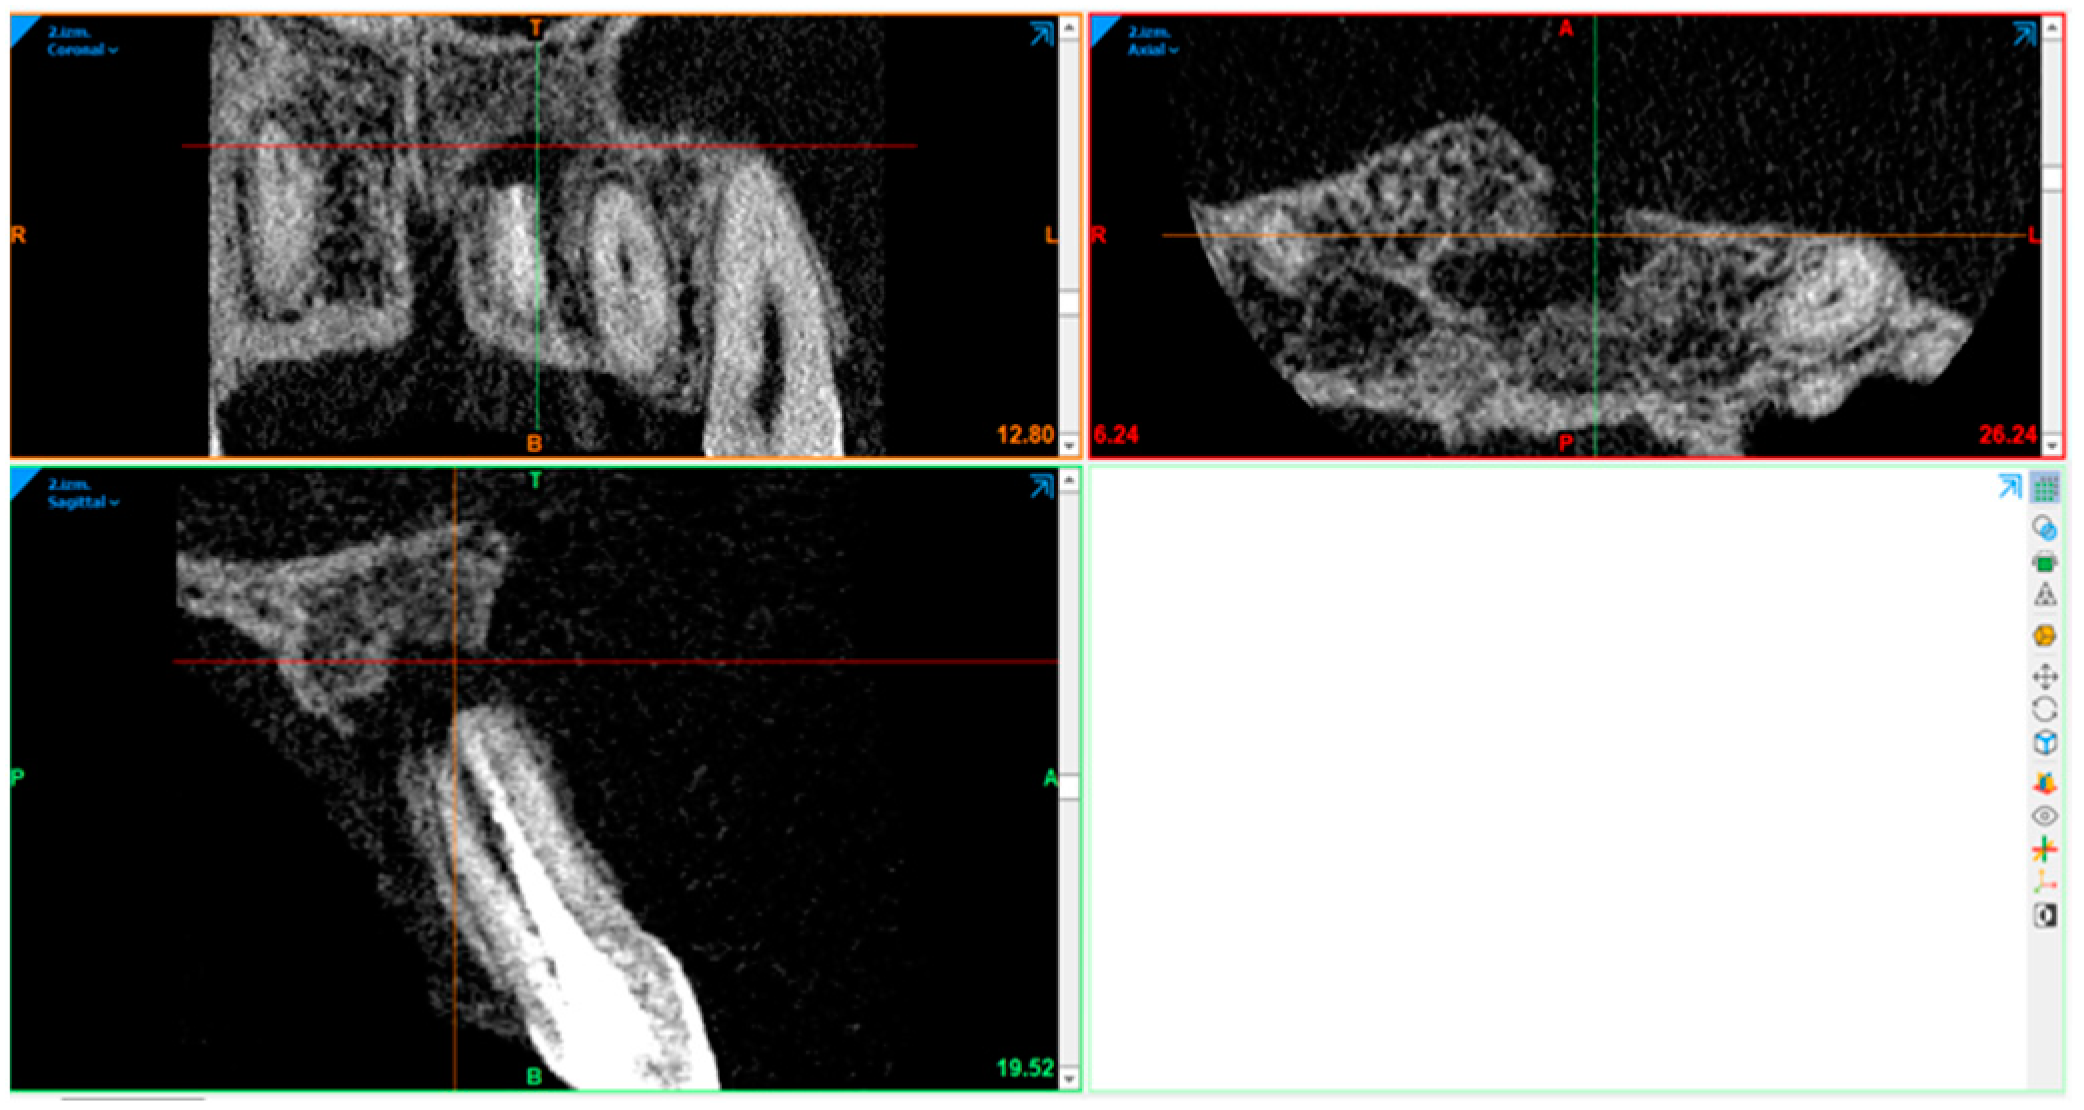

2.10. Radiography Acquisition: Volumetric Assessment

2.11. Statistical Analysis